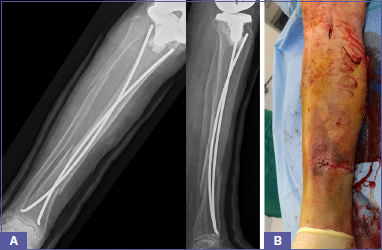

The second patient was a, 80-year-old male who suffered an open Gustilo-Anderson type I fracture of the left proximal tibial metaphysis (AO OTA Type 41A2) distal to a well-fixed TKA (Felix type IIIA) after a fall from the stairs (Fig. 3A). After 2 days open reduction and internal fixation (ORIF) with lateral plate and screws was performed with no complications. The limb was restrained with a brace. Due to local swelling and redness around the scar, the patient underwent surgical debridement and hematoma evacuation 5 days later and antibiotic prophylaxis was administered. Skin conditions progressively improved and the patient was discharged 16 days after the osteosynthesis in good clinical conditions. He was mobilized with toe-touch weight bearing with knee brace support for two months. Progressive passive articular kinesis was performed from the third post-operative day.

Radiographic imaging of the second case treated with ORIF demonstrated complete bone healing 6 months after the surgery (Fig. 3B). At the 12 month follow-up visit the patient reported no pain with full weight bearing with no aids. The flexion ROM was 120° and the KSS was 82 points.

Figure 3.A) 80-year-old male with a Felix type IIIA periprosthetic tibial fracture who was treated with open reduction and synthesis with plate and screws; B) X-ray after 6 months of follow-up.